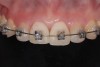

Fig 2. Orthodontic treatment with invisible appliances.

Figure 2

Invisalign® arch alignment (Figure 2) was used to resolve the Bolton discrepancy by expanding the upper and lower arches. This would result in upper incisor diastemas, which initially would emphasize the incisive lateral microdontia but would subsequently be restored with porcelain veneers.

The two central incisor crowns were replaced with new provisionals, and composite was used to restore her canines. Following this, fixed orthodontic therapy was started. The intention was to lingually displace and intrude the anterior teeth and reduce their torque (Figure 12).